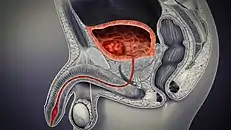

Cancer

Cancer of the bladder is known as bladder cancer. It is usually due to cancer of the urothelium, the cells that line the surface of the bladder. Bladder cancer is more common after the age of 40, and more common in men than women;[29] other risk factors include smoking and exposure to dyes such as aromatic amines and aldehydes.[29] When cancer is present, the most common symptom in an affected person is blood in the urine; a physical medical examination may be otherwise normal, except in late disease.[29] Bladder cancer is most often due to cancer of the cells lining the ureter, called transitional cell carcinoma, although it can more rarely occur as a squamous cell carcinoma if the type of cells lining the urethra have changed due to chronic inflammation, such as due to stones or schistosomiasis.[29]

Investigations performed usually include collecting a sample of urine for an inspection for malignant cells under a microscope, called cytology, as well as medical imaging by a CT urogram or ultrasound.[29] If a concerning lesion is seen, a flexible camera may be inserted into the bladder, called cystoscopy, in order to view the lesion and take a biopsy, and a CT scan will be performed of other body parts (a CT scan of the chest, abdomen and pelvis) to look for additional metastatic lesions.[29]

Treatment depends on the cancer's stage. Cancer present only in the bladder may be removed surgically via cystoscopy; an injection of the chemotherapeutic mitomycin C may be performed at the same time.[29] Cancers that are high grade may be treated with an injection of the BCG vaccine into the bladder wall, and may require surgical removal if it does not resolve.[29] Cancer that is invading through the bladder wall may be managed by complete surgical removal of the bladder (radical cystectomy), with the ureters diverted into a segment of part of ileum connected to a stoma bag on the skin.[29] Prognosis can vary markedly depending on the cancer's stage and grade, with a better prognosis associated with tumours found only in the bladder, that are low grade, that do not invade through the bladder wall, and that is papillary in visual appearance.[29]